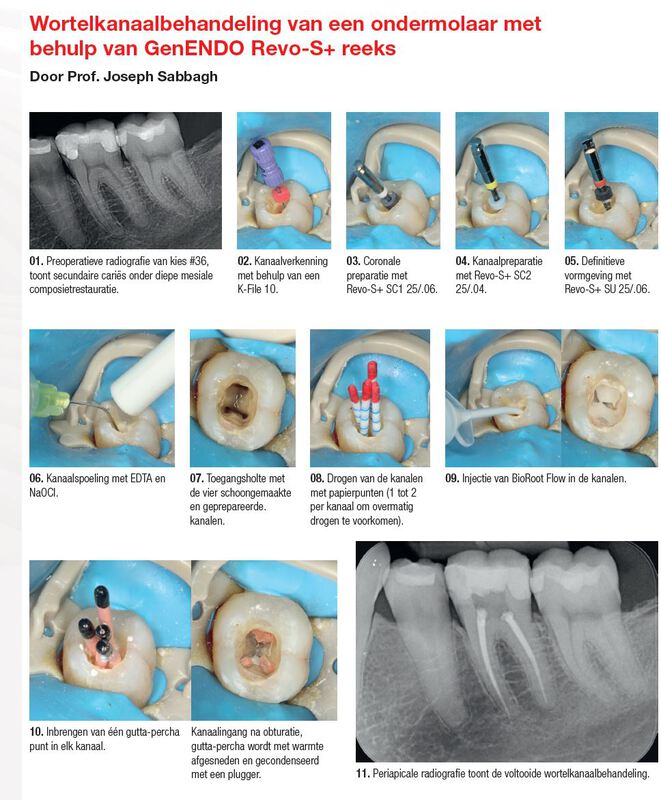

GenENDO Revo-S+ / 3-vijl reeks / 2 verschillende doorsneden / Steriel

Vereenvoudigd protocol, zonder compromis:

- Revo-S+: een korte reeks roterende vijlen

- Weinig stappen

- Snelle procedure